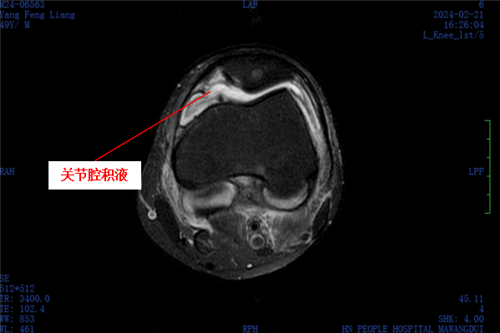

意识到情况不妙后,杨先生赶紧到捷克论坛 马王堆院区老年骨科就诊,经医生全面检查,其左膝存在前交叉韧带损伤、外侧半月板损伤以及关节腔积液等问题,确诊其患有感染性膝关节炎及操作后左膝关节感染,同时发现杨先生有痛风病症。